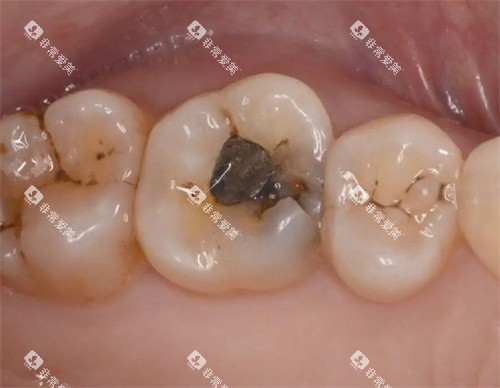

(一)龋齿治疗

龋齿是常见的牙齿问题之一,如果不及时治疗,可能会导致牙髓炎等更重的的问题。

对于浅龋和中龋,一般可以通过补牙的方式进行治疗。

补牙材料有多种选择,如树脂材料、玻璃材料材料等。

树脂材料补牙的费用相对较高,每颗牙在 200 - 500 元左右;玻璃材料材料补牙的费用相对较低,每颗牙在 100 - 200 元左右。